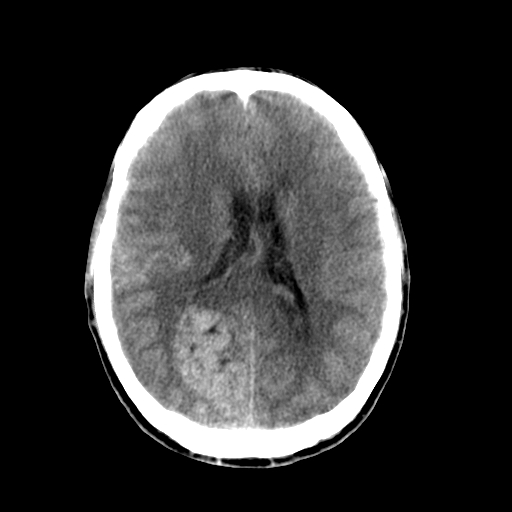

标题: CT17002:M48Y,血管畸形,血管瘤,请鉴赏! [打印本页]

标题: CT17002:M48Y,血管畸形,血管瘤,请鉴赏!

男48y,头痛多年,加重一天!

典型的血管畸形---avm  -----右侧枕顶叶及侧脑室三角区等高混杂密度影夹杂少许低密影显示,无明显水肿,增强可见明显的供血动脉与引流静脉显示